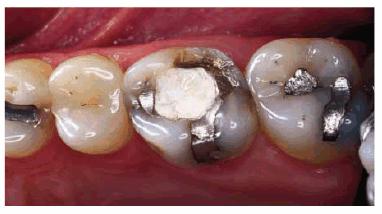

the amalgam-tooth interface (Figur 323s1823d es 18-12A 18-12B 18-12C 18-12D 18-12E, and 18-12F

Figur 323s1823d e 18-12A: Periapical radiograph showing tooth #30 after successful root canal treatment.

Figur 323s1823d e 18-12B: Bitewing radiograph showing tooth #30 with amalgam core build-up completed. Note that the core material extends approximately 2 mm into the canal orifices for increased retention.

Figur 323s1823d e 18-12C: Tooth #14 after successful root canal treatment.

Figur 323s1823d e 18-12D: Removal of temporary restorative material and remaining amalgam. Gutta-percha from the pulp chamber was removed for core retention.

Figur 323s1823d e 18-12E: Completed core build-up on tooth #14.

Figur 323s1823d e 18-12F: Completed crown preparation on tooth #14.